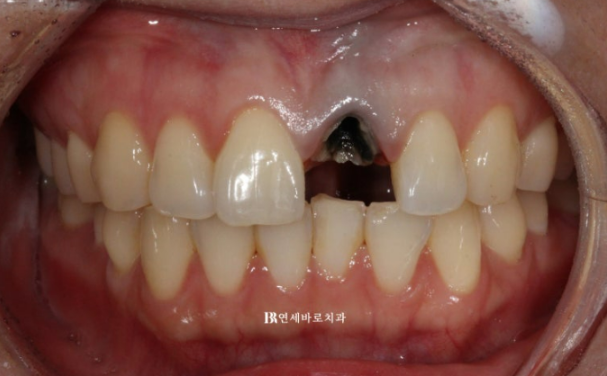

앞니가 부러져서 임플란트와 뼈이식을 해야한다 라는 내용을 듣고 오신 분입니다.

당장 빼고 임플란트 하기 전 혹시나 교정으로 살려 쓰는 방법도 있지 않을까 하여 찾아오신 분입니다.

치아가 부러진 위치가 뿌리여서 지금상태로는 크라운으로 회복이 불가능하니 발치하는 방법 밖에 없습니다.

하지만 교정으로 치아를 뼈속부터 끌어내려 정출시키면 크라운 해서 살려 쓸 수 있습니다.

부러진 치아가 까맣게 변색이 되어서 잇몸이 어둡게 비쳐 보이는 부분도 교정으로 어느정도는 가릴 수 있습니다.